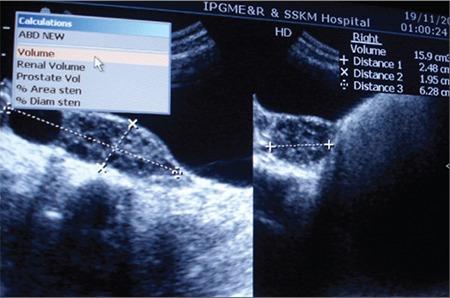

Department of Endocrinology and Metabolism, IPGMER and SSKM Hospital, Kolkata, India.

Syndrome of extreme insulin resistance (SEIR) is a rare spectrum disorder with a primary defect in insulin receptor signalling, noted primarily in children, and is often difficult to diagnose due to the clinical heterogeneity.SEIR was diagnosed in an adolescent girl with facial dysmorphism,exuberant scalp and body hair, severe acanthosis, lipoatrophy, dental abnormalities, and short stature (Rabson-Mendenhall phenotype). She had elevated fasting (422.95 pmol/L) and post-glucose insulin levels(>2083 pmol/L). Total body fat was decreased (11%; dual-energy X-ray absorptiometry). Basal growth hormone (GH) was increased (7.9 μg/L)with normal insuline-like growth factor 1 (37.6 nmol/L) suggestive of GH resistance. She had fatty liver and polycystic ovaries. Echocardiography revealed ostium secundum type atrial septal defect (ASD). Blood glucose normalized with pioglitazone (30 mg/day). Delayed development, severe insulin resistance, mild hyperglycemia, absence of ketosis, and remarkable response of hyperinsulinemia and hyperglycemia to pioglitazone which persisted even after 1 year of diagnosis are some of the notable features of this patient. This is perhaps the first report of occurrence of congenital heart disease (ASD) in a patient of SEIR (Rabson-Mendenhall phenotype). This report highlights the clinical features of SEIR and the role of insulin sensitizers like pioglitazone in the management of such patients.

极端胰岛素抵抗综合征(SEIR)是一种罕见的谱系障碍,主要缺陷在于胰岛素受体信号传导,主要见于儿童,由于临床异质性,往往难以诊断。一名患有面部畸形、头皮和身体毛发旺盛、严重棘皮症、脂肪萎缩、牙齿异常和身材矮小(拉布森 - 门登霍尔表型)的青春期女孩被诊断为SEIR。她的空腹胰岛素水平升高(422.95 pmol/L),葡萄糖后胰岛素水平升高(>2083 pmol/L)。全身脂肪减少(11%;双能X线吸收法)。基础生长激素(GH)升高(7.9 μg/L),胰岛素样生长因子1正常(37.6 nmol/L),提示存在GH抵抗。她患有脂肪肝和多囊卵巢。超声心动图显示继发孔型房间隔缺损(ASD)。使用吡格列酮(30 mg/天)后血糖恢复正常。发育迟缓、严重胰岛素抵抗、轻度高血糖、无酮症以及高胰岛素血症和高血糖对吡格列酮有显著反应且在诊断后1年仍持续存在,这些都是该患者的一些显著特征。这可能是首例关于SEIR(拉布森 - 门登霍尔表型)患者发生先天性心脏病(ASD)的报告。本报告强调了SEIR的临床特征以及胰岛素增敏剂如吡格列酮在这类患者管理中的作用。